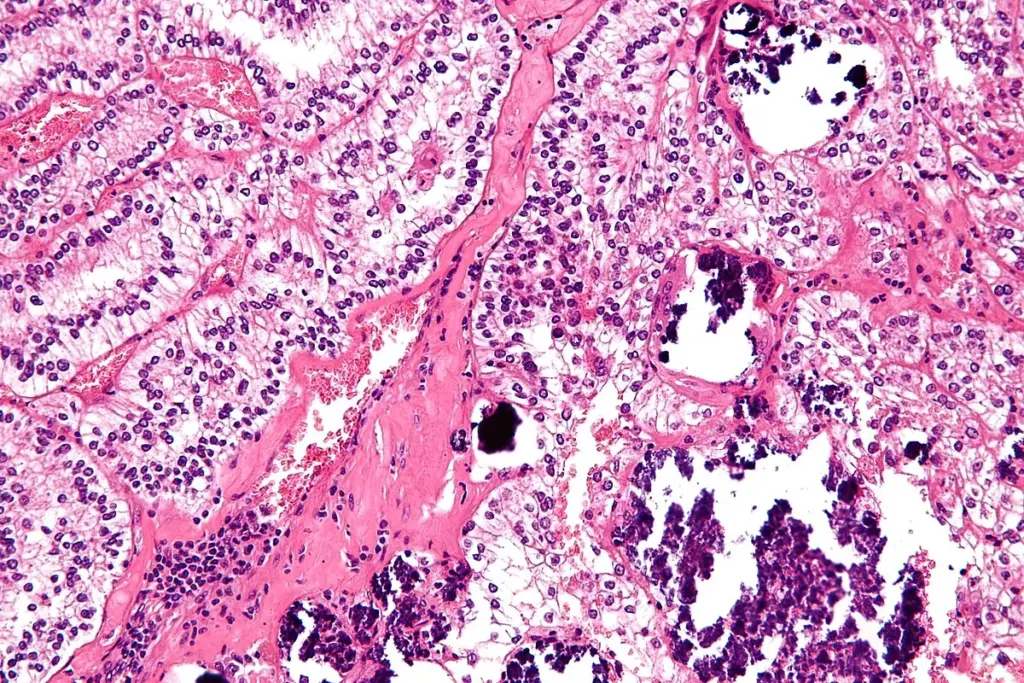

The Diagnostic Process: From Symptom to Biopsy

When a symptom suggests cancer, a doctor will begin with a thorough physical exam and a review of medical history. If a specific area is suspected, the next step is typically an imaging test to visualize the inside of the body. However, cancer can only be confirmed with a biopsy. This procedure involves a specialist (such as a surgeon or radiologist) taking a sample of the suspicious tissue. A pathologist then analyzes these cells under a microscope to confirm the presence of cancer and identify its specific type.